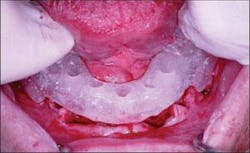

The interim denture was then placed intraorally and a bite registration made (Figure 4) to be utilized in the conversion of this removable prosthesis to the fixed provisional restoration. This registration will be utilized for reapproximation of the denture intraorally once the dental implants and appropriate abutments have been placed.

Figure 4 - Bite registration with interim denture in place